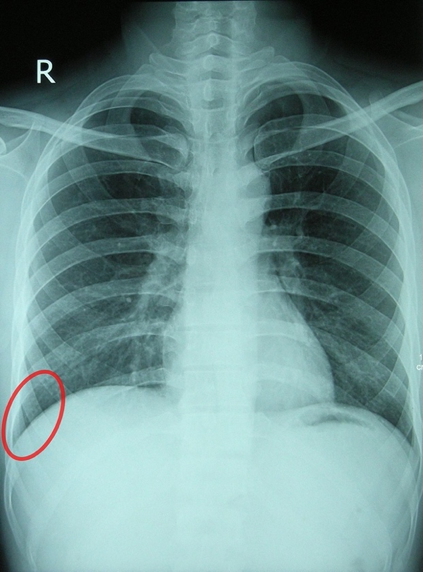

- Continuous serous sacs: visceral pleura (covers lungs) & parietal pleura (lines thoracic cavity)

- Costodiaphragmatic recess: potential space for lung expansion during forced inspiration